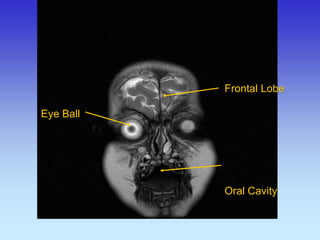

Eye Ball

Frontal Lobe Oral Cavity